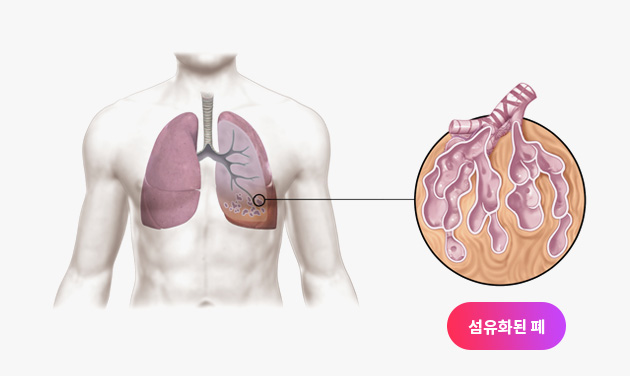

특발성폐섬유증과 같은 간질성폐질환은 예후가 좋지 못하다고 알려진 병입니다. 하지만 한약 치료를 통해 이 병을 극복하려는 노력이 진행되고 있습니다.